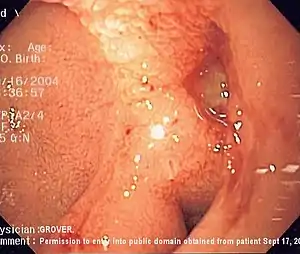

| Endoscopic image of a posterior wall duodenal ulcer with a clean base, a common cause of upper gastrointestinal bleeding. | |